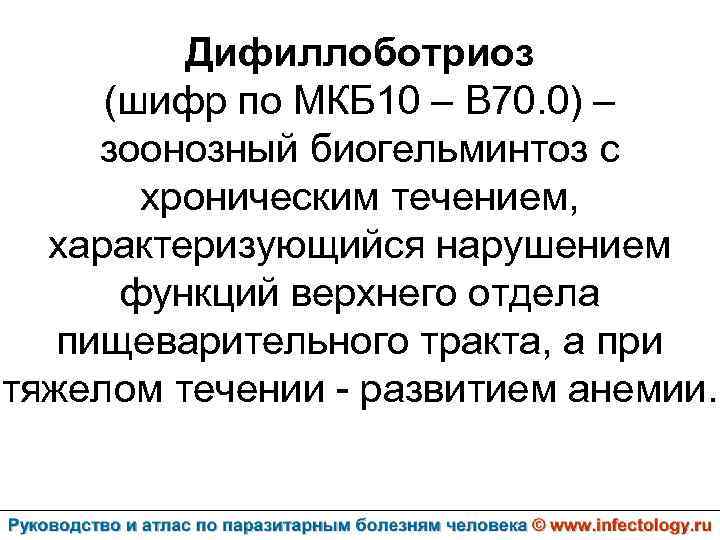

Дифиллоботриоз (шифр по МКБ 10 – B 70. 0) – зоонозный биогельминтоз с хроническим течением, характеризующийся нарушением функций верхнего отдела пищеварительного тракта, а при тяжелом течении - развитием анемии.